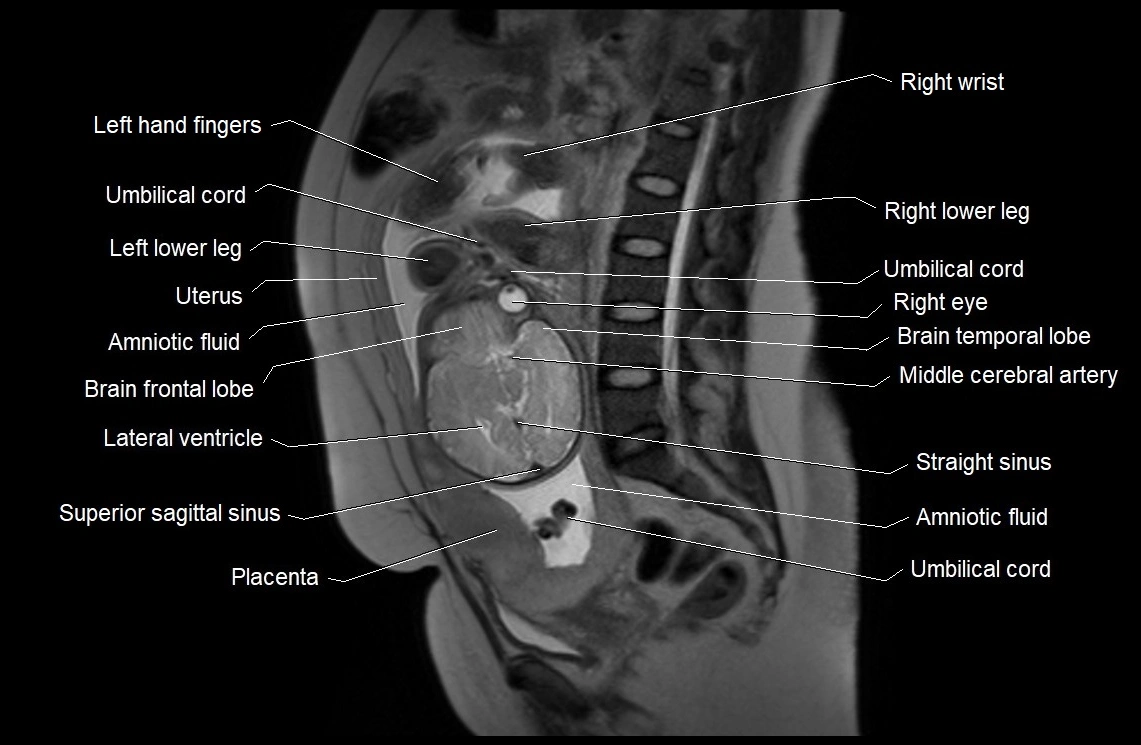

MRI Appearance

T2 HASTE (T2 GRE):

• Amniotic fluid shows very bright hyperintense signal

• Provides natural contrast against fetus and placenta

• Small particles (vernix) may appear as scattered hypointense foci within bright fluid

T1 GRE:

• Amniotic fluid shows low signal intensity (dark)

• Hemorrhage, infection, or proteinaceous content may cause focal or diffuse high signal intensity

MRI image

image